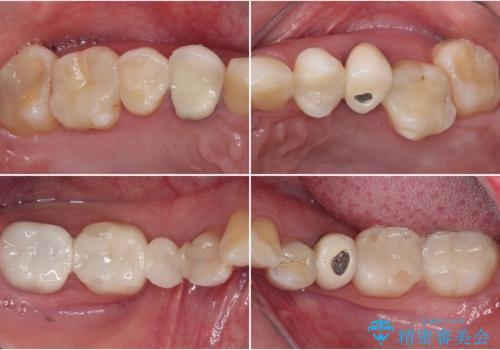

- クラウンから金属の土台が見えてきてしまったとのことで、作り替えを希望して来院された患者様です。

前歯や金属が露出している歯、痛みを感じる歯を中心に、オールセラミッククラウンにて補綴治療することとしました。